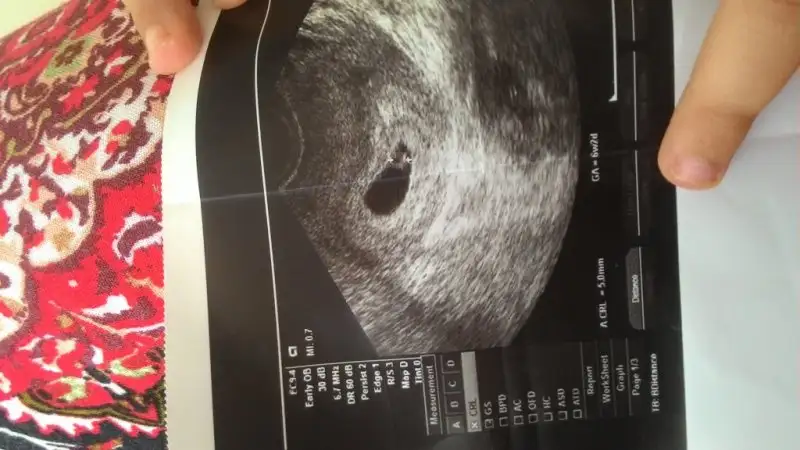

yabancı sitelere baktım canım. bebek ile plasenta daha 6 ya da 7 haftalıkken birbirinden uzak olabiliryormuş. bir kaç foto ekliyorum. bu ultrasonlar vajinal. ( bu arada bu bebişlerde plasenta yönü yani ramzi teorisi tutmuş)Cnm bu konuda bi karara varabilmemiz için burdaki plasentası sağda veya solda dediğimiz arkadaşlardan bi cvp gelmesi bizimde ona göre işe yarayıp yaramadıgını öğrenmemiz gerekiyo. Fakat çoğu daha cinsiyeti öğrenemedi galiba. Ben öğrenenlerin eski usglerine bakıorm bi kaç tane tuttu yani plasenta ve bebek solda oğlu olcakmş. Ama bi kaç tane tutması istisna olabilir canım. Ben hiçbi teoriye %100 doğru diyemem.

Evet canım bende okumuştum zaten bebekle plasentanın farklı yerlerde olduğunu biliyorum. Slvestr arkadaşımız bebek nerdeyse plasentada orda olur demişti. Ama öyle değil. Benim ilk gebeliğimde bariz bebek solda hatta en sola yapışık yani. Ama plasenta sağda ve benim 11 aylık bir cimcimem var. Yani plasenta olayı ilk gebeliğimde tuttu. Şimdi bebekte plasentada solda bakalım sonuç ne olacak. Eğer yine kızım olursa plasenta olayı yalan arkadaşlar. Tutanlar tesadüf dicez napalımyabancı sitelere baktım canım. bebek ile plasenta daha 6 ya da 7 haftalıkken birbirinden uzak olabiliryormuş. bir kaç foto ekliyorum. bu ultrasonlar vajinal. ( bu arada bu bebişlerde plasenta yönü yani ramzi teorisi tutmuş)

yabancı sitelere baktım canım. bebek ile plasenta daha 6 ya da 7 haftalıkken birbirinden uzak olabiliryormuş. bir kaç foto ekliyorum. bu ultrasonlar vajinal. ( bu arada bu bebişlerde plasenta yönü yani ramzi teorisi tutmuş)